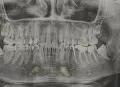

Я как многие девушки хотела бы красивую улыбку, да ещё за короткий срок и за приятную мне сумму. С зубами у меня проблем как бы нет, к стоматологу я вообще не хожу. Хоть они у меня кривые с детства. Если ближе к делу у меня такая проблема видно на фото.

Мне нужно брекеты носить или виниры возможно сделать? Что по стоимость дешевле брекеты или виниры?

В вашем случае требуется ортодонтическое лечение (брекет-система, элайнеры). Цена зависит от статуса клиники, региона обращения и выбранной системы и может варьировать от 70 000-300 000 руб.